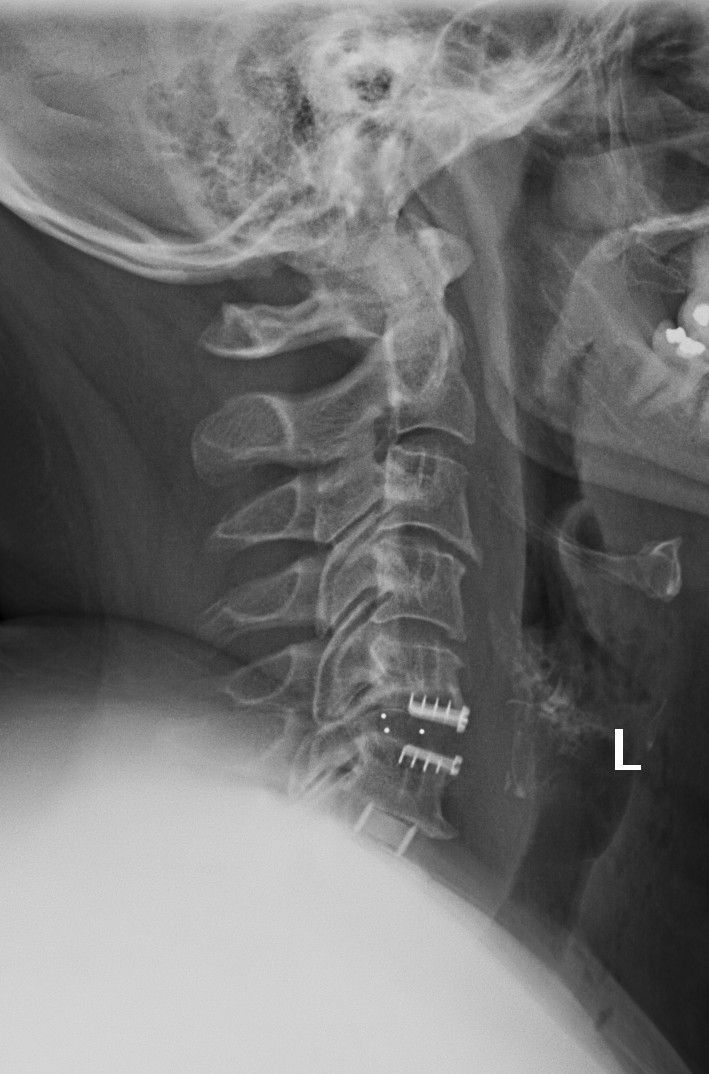

Zdjęcia i filmy